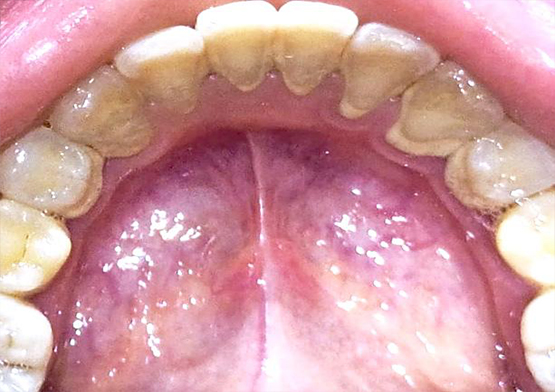

Before Scalling

After Scalling